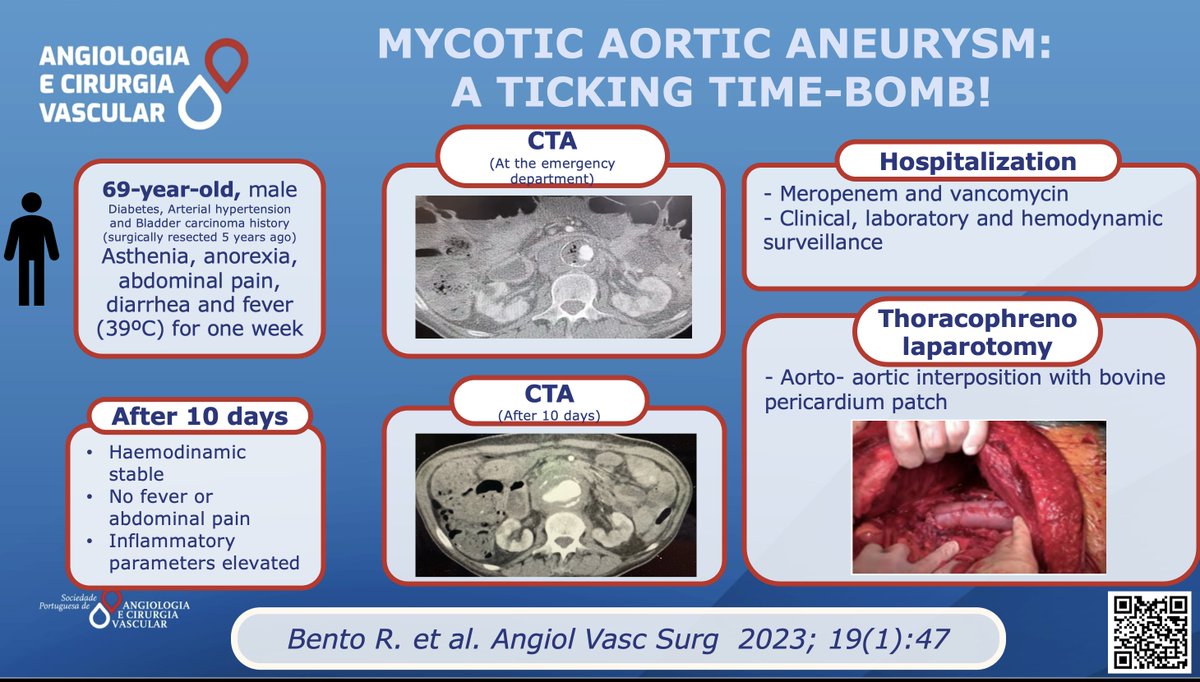

Open surgery and an aorto- aortic interposition with bovine pericardium patch was the treatment choice of Bento R. et al. Read more here: acvjournal.com/index.php/acv/… #spacv #vascularsurgery #mycoticaorticaneurysms #vascularinfections ESVS Society for Vascular Surgery Vascular News